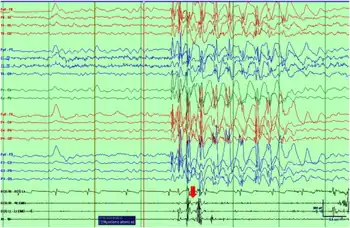

| Ictal EEG with polygraphy of a myoclonic–atonic seizure shows initial myoclonus associated with the burst of polyspikes and atonia on the EMG associated with slow wave component of the discharge | |

The onset of seizures is between the ages of 2 and 5 years of age. EEG shows regular and irregular bilaterally synchronous 2- to 3-Hz spike-waves and polyspike patterns with a 4- to 7-Hz background. 84% of affected children show normal development prior to seizures; the remainder show moderate psychomotor retardation mainly affecting speech. Boys (74%) are more often affected than girls (Doose and Baier 1987a).[2]